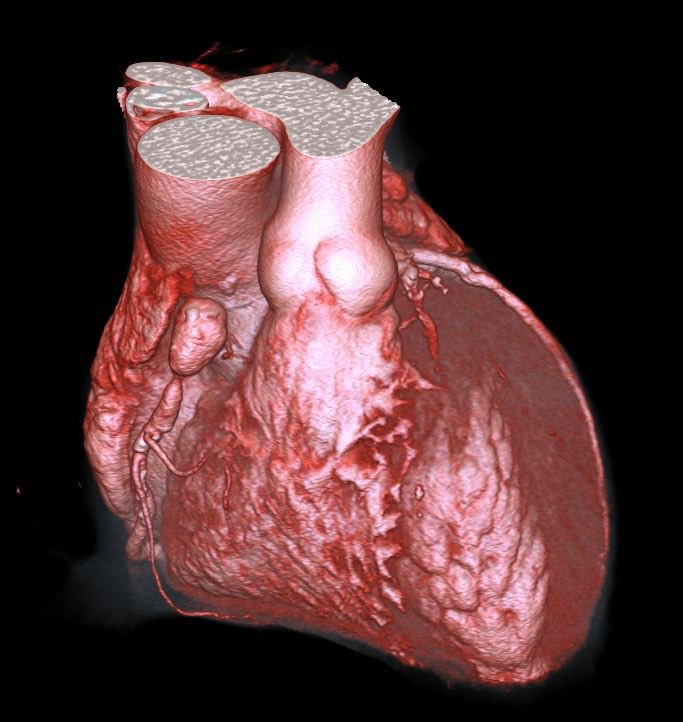

Postaneurysmal high-grade stenosis of the right coronary artery in the cardiac CT with the corresponding findings of the coronary angiography before and after stenting. What a beautiful case! @Steph_Achenbach @M_Marwan_ @monique_trobs @escardio @Heart_SCCT

0

2

5